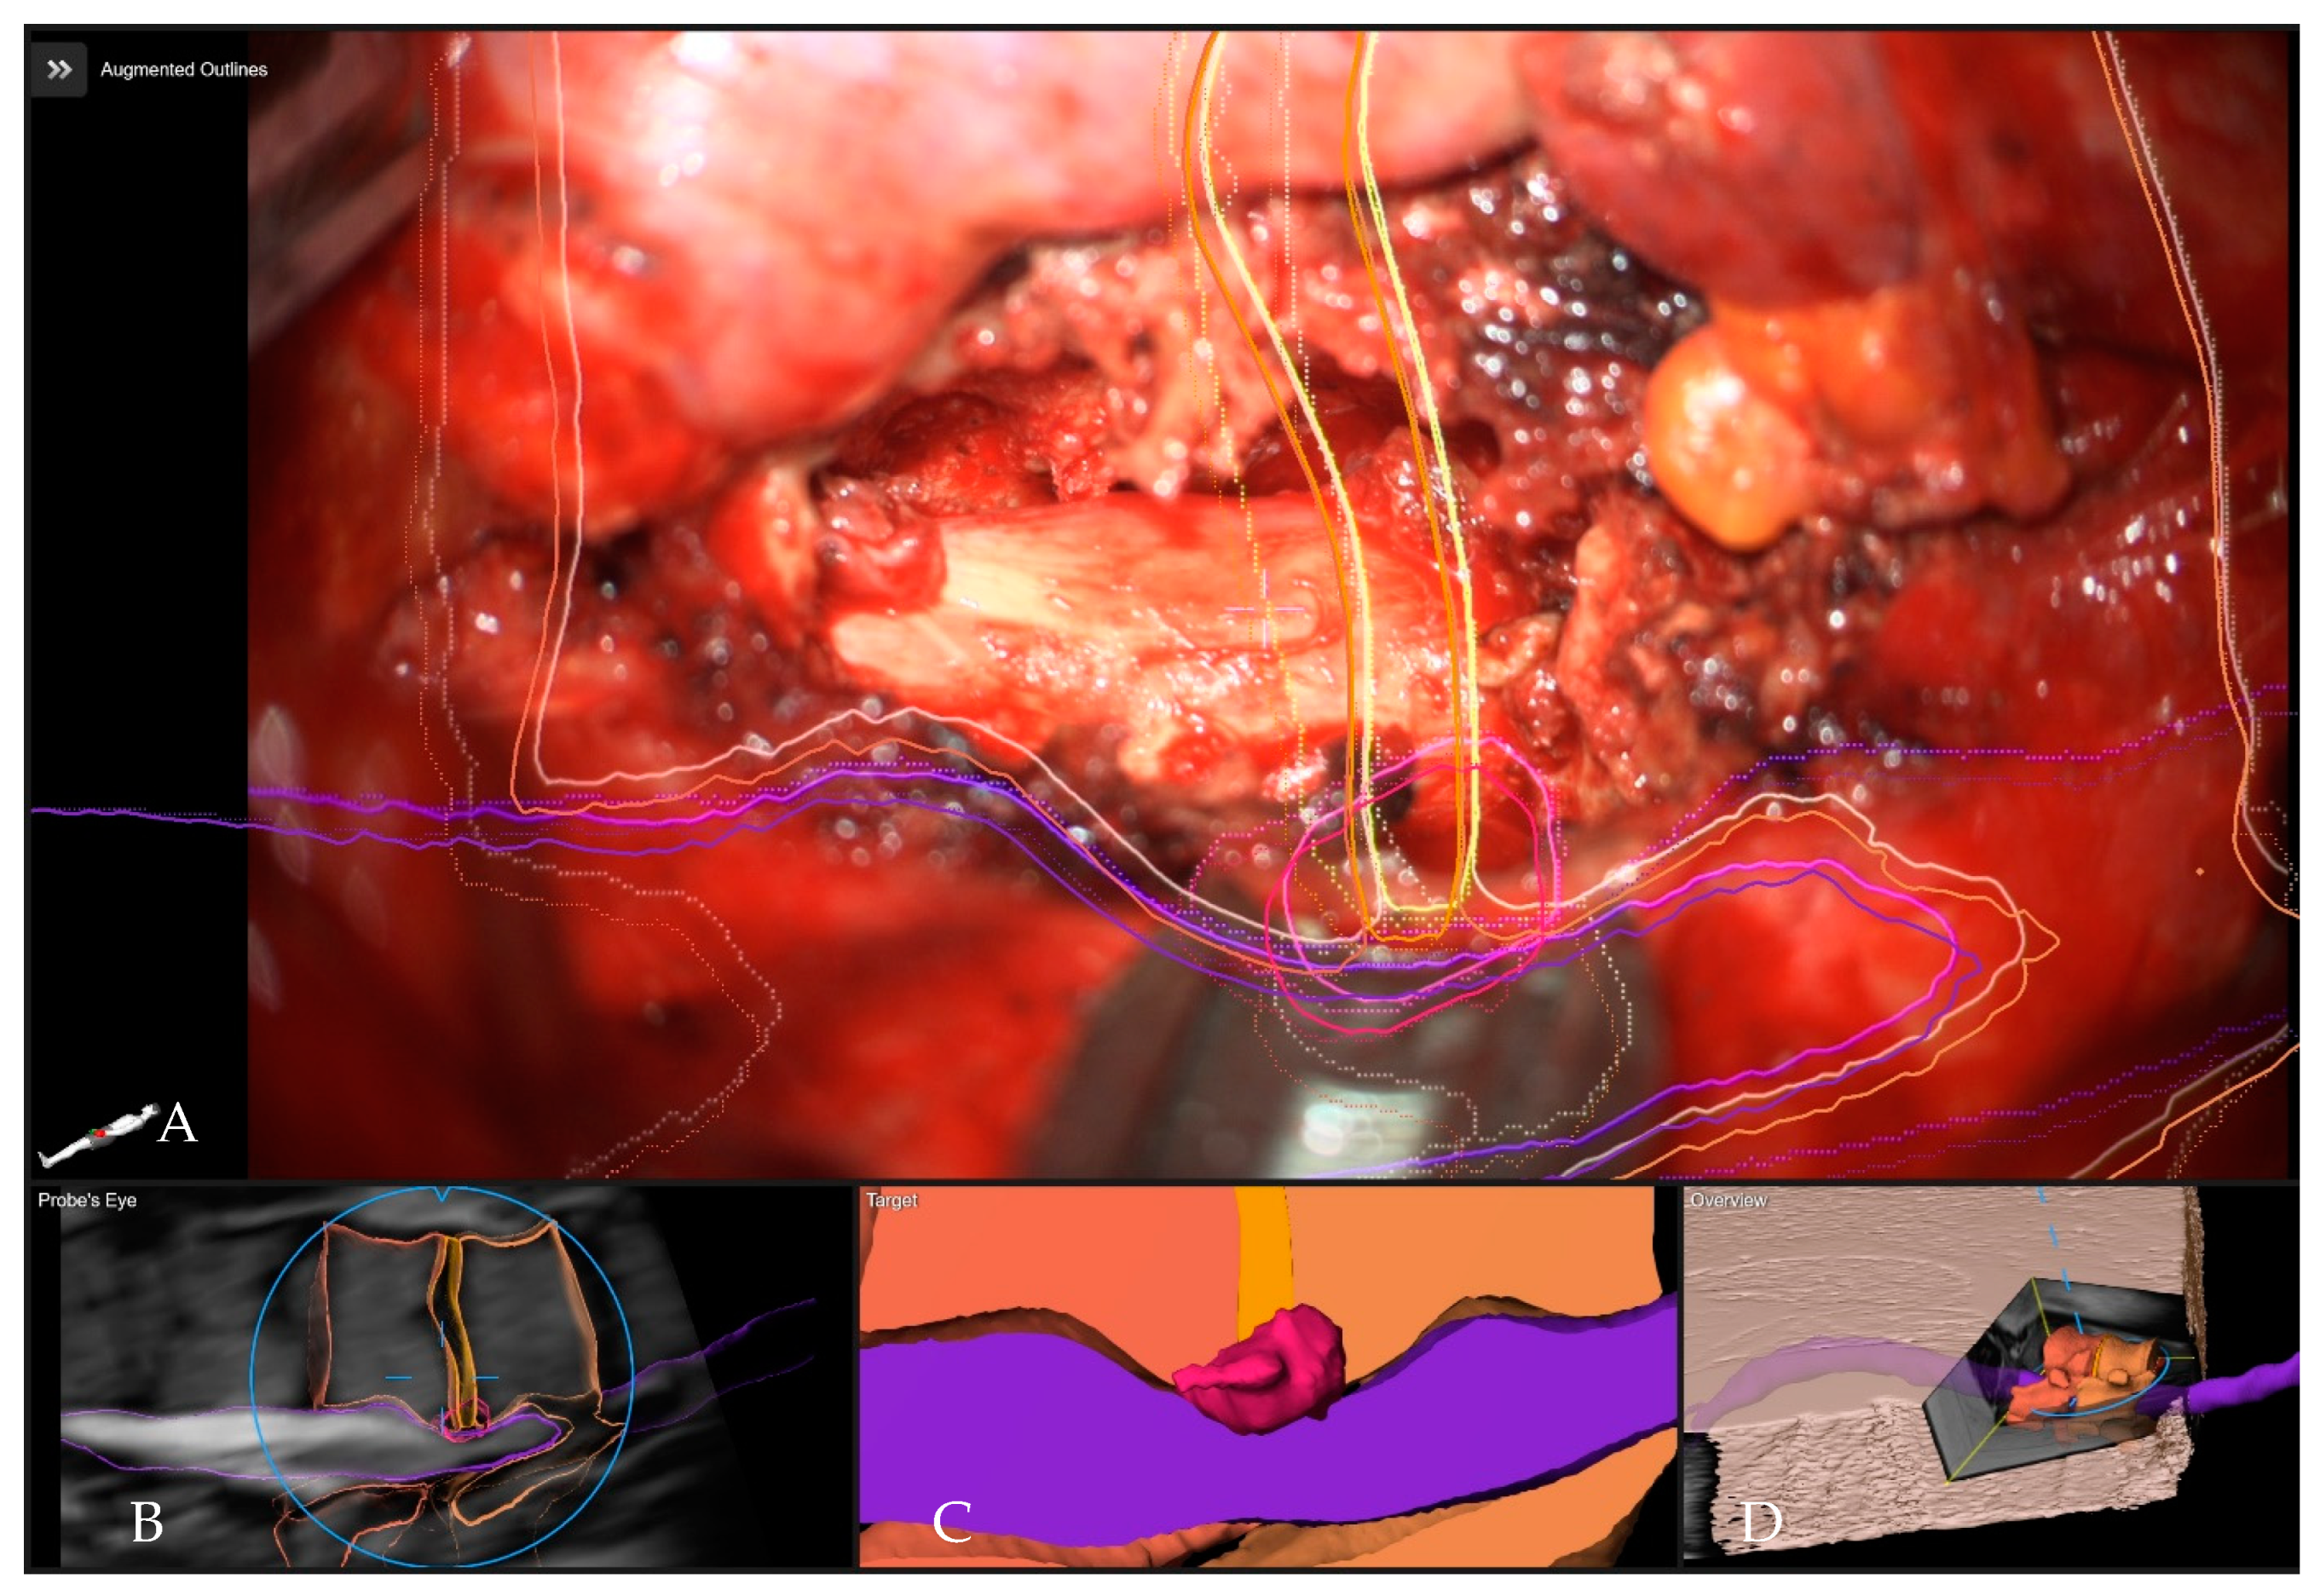

- Pojskić, M.; Bopp, M.; Saß, B.; Kirschbaum, A.; Nimsky, C.; Carl, B. Intraoperative Computed Tomography-Based Navigation with Augmented Reality for Lateral Approaches to the Spine. Brain Sci. 2021, 11, 646. [Google Scholar] [CrossRef] [PubMed]

- Carl, B.; Bopp, M.; Saß, B.; Pojskic, M.; Nimsky, C. Augmented reality in intradural spinal tumor surgery. Acta Neurochir. 2019, 161, 2181–2193. [Google Scholar] [CrossRef] [PubMed]

- Carl, B.; Bopp, M.; Saß, B.; Pojskic, M.; Voellger, B.; Nimsky, C. Spine Surgery Supported by Augmented Reality. Glob. Spine J. 2020, 10 (Suppl. 2), 41S–55S. [Google Scholar] [CrossRef]

- Carl, B.; Bopp, M.; Saß, B.; Voellger, B.; Nimsky, C. Implementation of augmented reality support in spine surgery. Eur. Spine J. 2019, 28, 1697–1711. [Google Scholar] [CrossRef]

- Carl, B.; Bopp, M.; Saß, B.; Nimsky, C. Microscope-Based Augmented Reality in Degenerative Spine Surgery: Initial Experience. World Neurosurg. 2019, 128, e541–e551. [Google Scholar] [CrossRef] [PubMed]